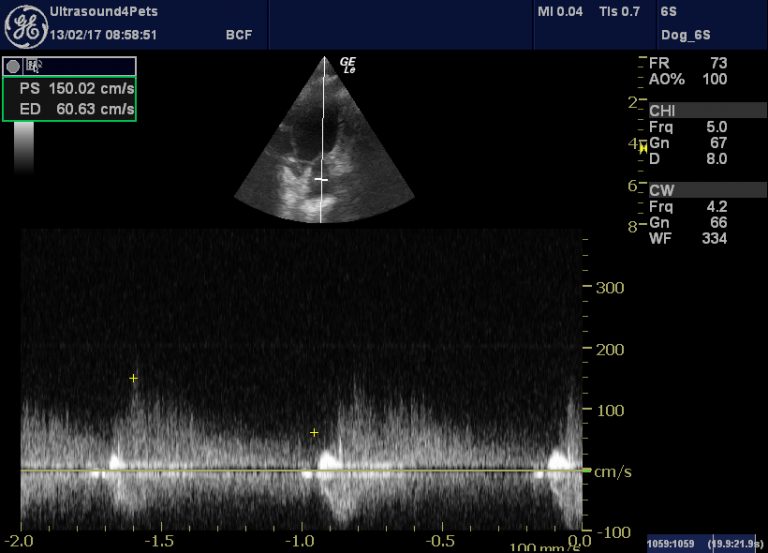

Canine patent ductus arteriosus (PDA) echocardiography Vet Practice What Is Pda In Dogs patent ductus arteriosus in dogs is a congenital heart disease that can be fatal. In a fetus, this vessel is normal and allows blood to. patent ductus arteriosus (pda) is a common form of congenital heart disease in dogs (schrope, 2015; patent ductus arteriosus (also called pda) is a birth defect in the heart. patent ductus. What Is Pda In Dogs.